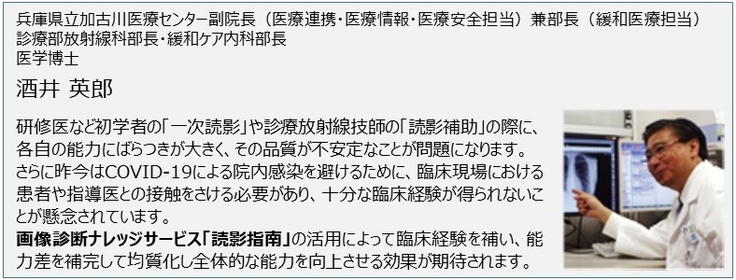

現在、”画像診断ナレッジサービス「読影指南」”は画像診断の精度向上に対する優位性が認められ、採用施設が増えつつあります。すでに”画像診断ナレッジサービス「読影指南」”を導入している兵庫県立加古川医療センターでは、研修医の臨床経験を補う目的でご利用いただいています。一方、診療放射線技師を養成している鈴鹿医療科学大学では、3,4年生全員が”画像診断ナレッジサービス「読影指南」”を用いて学習しています。このように既に医師や技師の育成にお使いいただいている施設では大変好評をいただいていますが、この機会に多くの医療機関などに”画像診断ナレッジサービス「読影指南」”を提供して、ひとりでも多くの医師や診療放射線技師の臨床経験を補うことにより画像診断の精度向上に役立てていきたいと考えています。その結果、疾患の早期発見により、患者やその家族の肉体的、経済的、さらには精神的な負担軽減に貢献することがメディカル指南車の願いです。